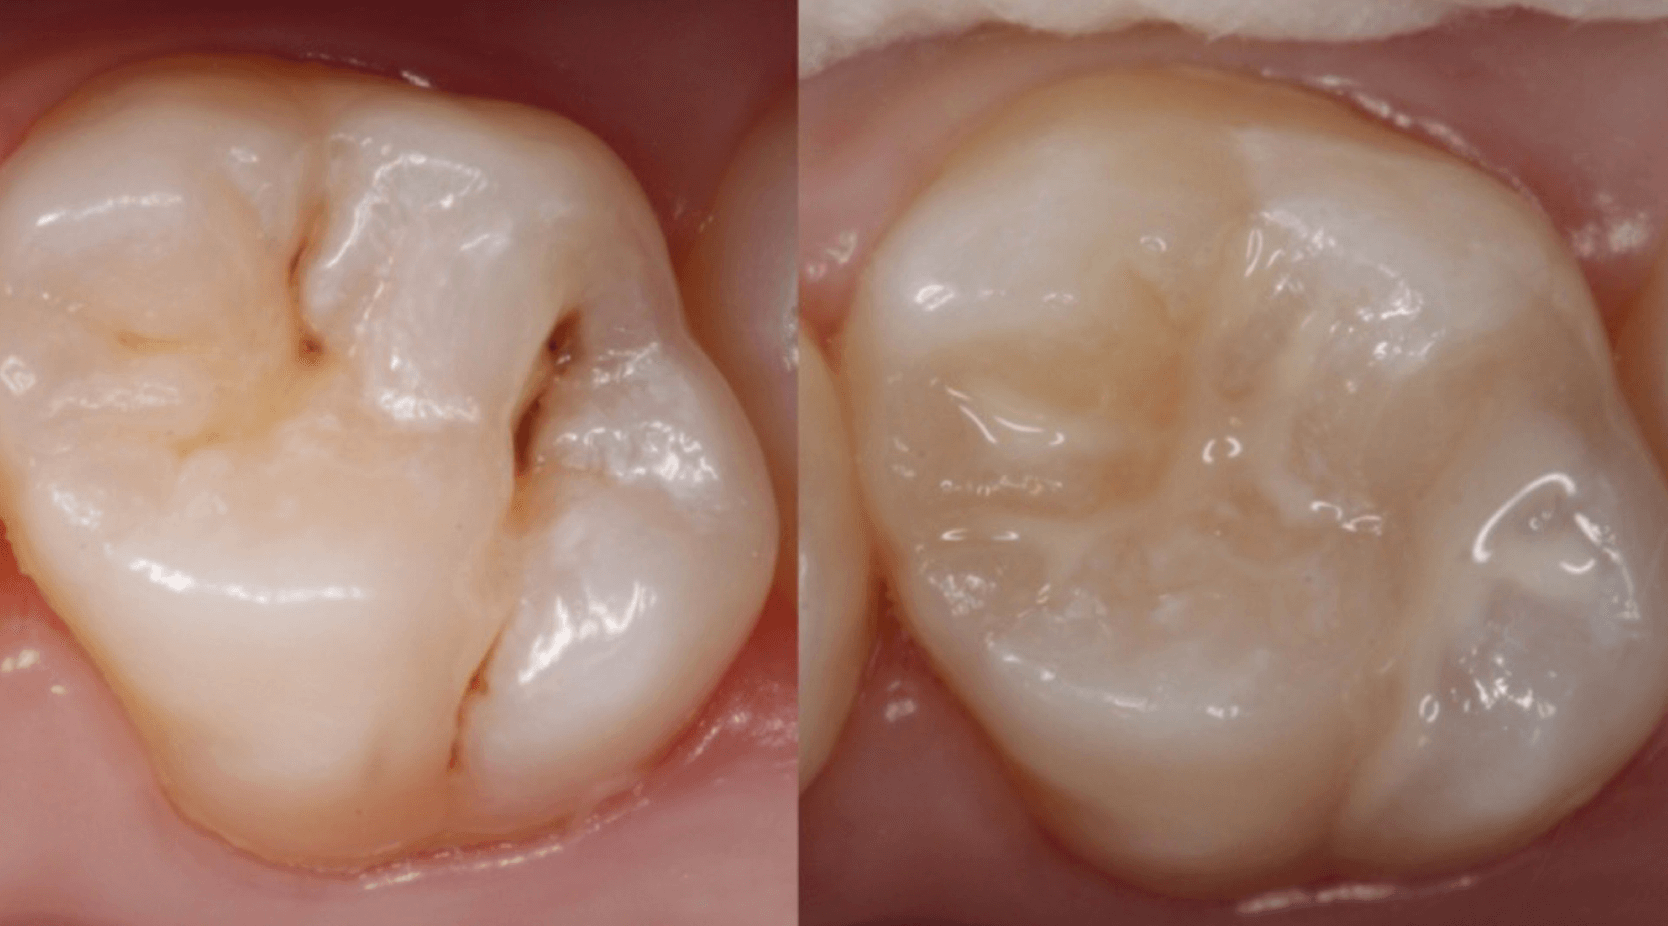

초등학생 같은경우 만12세 까지 레진 치료 비용이 보험적용을 받을수 있어 보다 저렴한 비용으로 충치 치료를 레진으로 받을수 있습니다. 중학생 1학년 이더라도 생일이 지나지 않았다면 보험적용 비용으로 레진을 할수 있으니 만12세까지 이러한 보헙적용 혜택을 놓치지 마세요.

초등학생 충치 치료 비용은 만 12세까지 보험적용을 받아 레진 한개당 2만5천원의 비용으로 떼울수 있습니다. 이러한 보험적용을 받지 않는다면 보통 레진 한개당 8만원에서 10만원까지 치과에서 받기 때문에 꼭 만12세전 충치 치료를 깔끔하게 하는것이 좋습니다.

초등학생 충치 치료시 레진으로 사용하면 만12세까지 2만 5천원의 비용으로 치료를 받을수 있지만, 이 기간이 지나면 치과에 따라 8만원 또는 12만원까지 하기 때문에 시기를 놓치지 마시고, 실제적으로 레진 충치치료 보험적용 기준은 아래와 같습니다.

이러한 기준으로 보면 치과에 따라 2 ~3만원 내의 초등학생 레진 치료 비용이 청구가 됩니다. 이때 충치의 범위가 너무 넓어서 레진으로 할수 없는경우 인레이로 치료를 해야 하는데 이런경우는 보험적용이 되지 않아 30만원 가량의 비용으로 인레이 치료를 받아야 합니다.